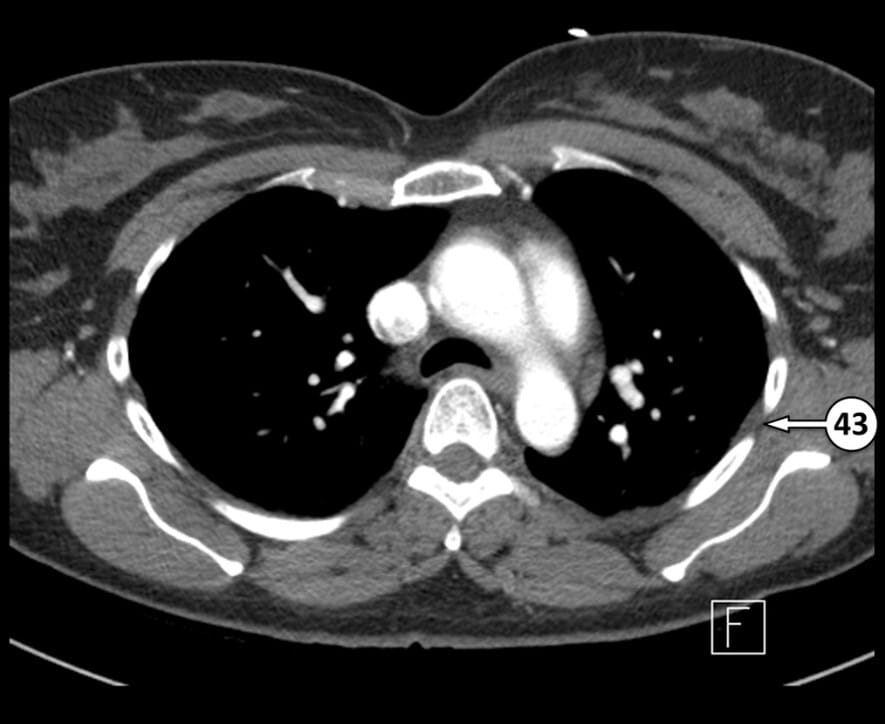

43. intercostal space